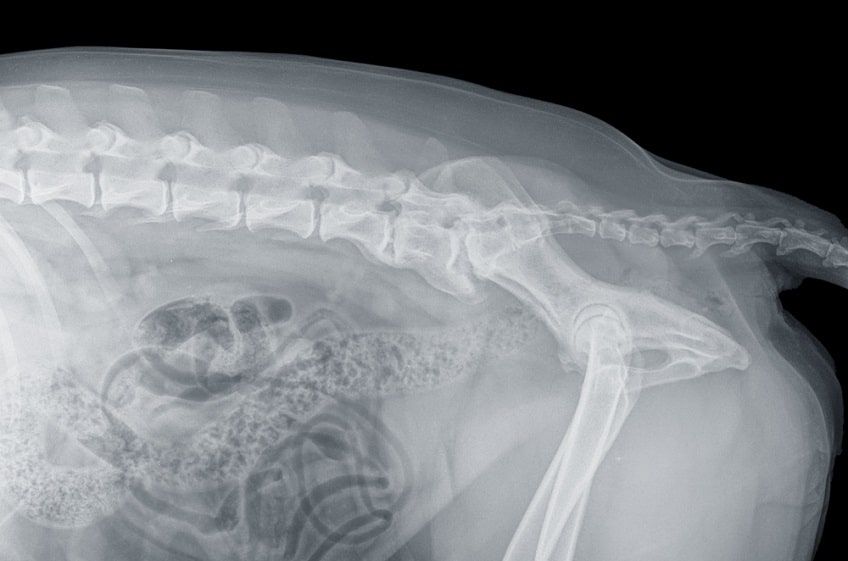

Pies, u którego istnieje podejrzenie wystąpienia choroby, powinien być poddany dokładnej diagnostyce obejmującej badanie neurologiczne i ortopedyczne. Neurolog weterynaryjny sprawdzi zakres ruchu w stawach psa, stan umięśnienia tylnych kończyn, odruchy neurologiczne i sposób poruszania się czworonoga. Następnie u psa pod narkozą należy wykonać kilka zdjęć RTG obrazujących stan kręgosłupa w odcinku lędźwiowo-krzyżowym, które pozwolą wykluczyć inne przyczyny objawów. W rozpoznanie zespołu ogona końskiego u psa pomocne są także inne badania obrazowe – tomografia komputerowa i rezonans magnetyczny.